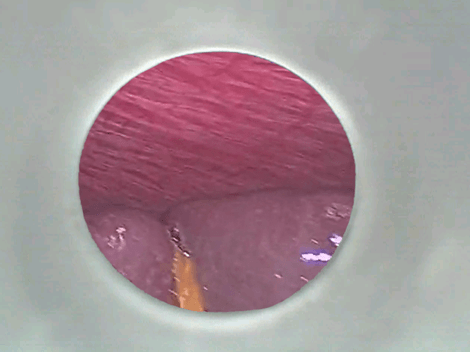

基于这款AR眼镜,理湃光晶在探索与医用腔镜结合,已经和其参股公司上海天慈理湃医疗科技完成了眼镜和腹腔镜无线协议的通讯对接,把腔镜前段拍摄的图像显示在眼镜镜片上。当医生利用腔镜器械实施微创手术的时候,既可以透过高度透明的镜片,操作相关手术器械,也可以在需要时在眼镜上观看病人体内的病灶组织,避免了传统手术时医生要在旁边的显示屏和手术器械之间频繁切换视野。图像传输的延时据称也缩短到了毫秒级。

天慈理湃已经把方案提供给一些医院,如第二军医大学附属长征医院骨科医院等,进行试用,从动物实验开始,论证可靠性和可行性,目前还没经过实际患者手术验证。许建表示,医生对新的眼镜有一个接受过程,很多医生都有兴趣,但不同医生对于图像有线还是无线传输,图像是否要放大等需求各有不同。同时由于腔镜种类也很多,不用品牌腔镜的通信协议也可能不同,面对各式不同的需求,理湃选择先从腹腔镜和骨腔镜入手,深入完成方案研发,之后再向其它品类拓展。